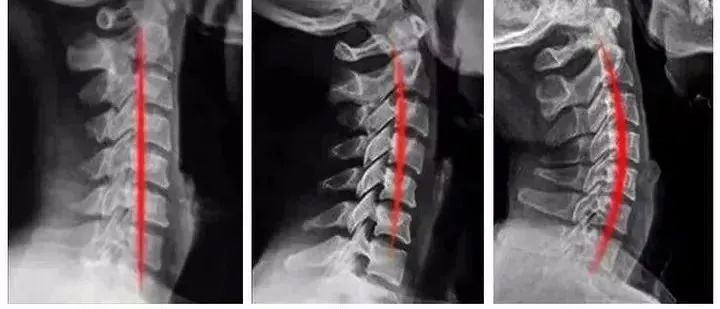

合理调整颈椎曲度